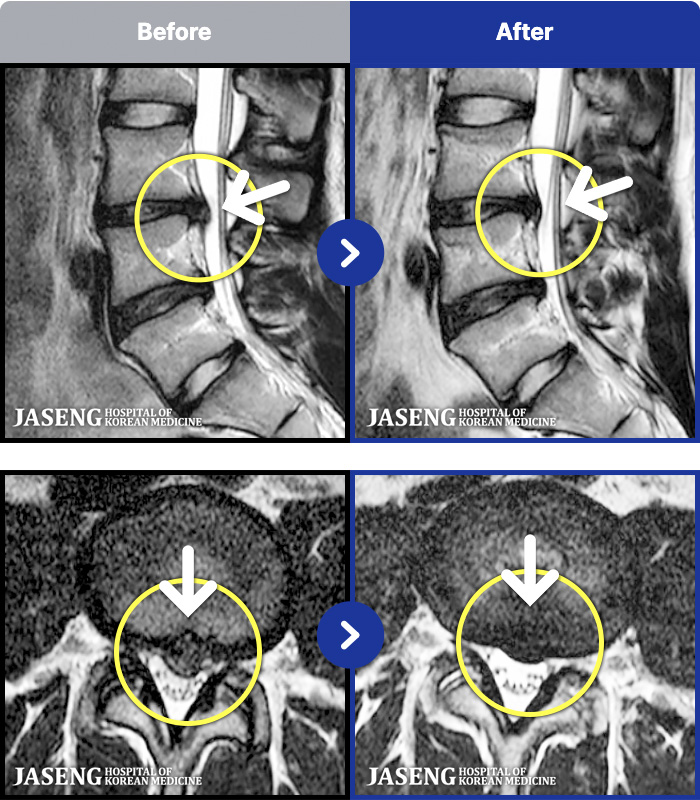

MRI ġ

1,245 MRI ũ ʸ Ȯϼ.